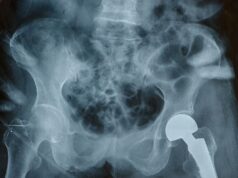

Rationing Joint Replacement Surgeries: Who Gets Priority in a Resource-Limited System?

If you work in orthopaedics, you know how challenging it can be to manage long waitlists for joint replacement surgeries. Limited resources mean not...